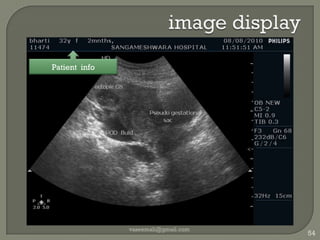

image displayvaseemali@gmail.com54Patient  info

image displayvaseemali@gmail.com55Profile / Preset